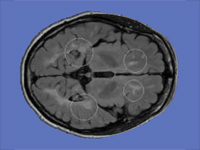

Integrative Visualization of Temporally Varying Medical Image Patterns

We present software for the visualization of temporal changes of disease patterns using stacks of medical images collected in time-series experiments. With this software users can generate 3D surface models representing disease patterns and observe changes over time in size, shape, and location of clinically significant image patterns. Statistical measurements of the volume of the observed disease patterns can also be obtained simultaneously.

Generation of Connectivity-Preserving Surface Models of Multiple Sclerosis Lesions

In this article we introduce a software tool to build 3D surface models of Multiple Sclerosis (MS) brain lesions from 2D image stacks typically obtained through Magnetic Resonance Imaging (MRI). This tool allows users to create 3D models of MS lesions quickly and visualize the lesions and brain tissue using various visual attributes and configurations.

A Novel MRI Visualization Tool for White Matter Pathology in Multiple Sclerosis

We developed a tool to visualize MS lesions and their 3D surface models to show changes in the lesions over time. These can be shown as an animation to elucidate differences across scanning sessions. With this software, a volumetric sub-region can be selected from the 3D model for zooming or animation, and a point on the 3D model can be selected to highlight all lesions connected to it. The total volume of lesions can be calculated, displayed as a chart, and exported.

Concurrent Visualization of and Mapping between 2D and 3D Medical Images for Disease Pattern Analysis

We present a software tool to highlight and display regions of interest in 2D medical images and their 3D mesh model counterparts. This tool can help researchers visualize and compare brain lesions and tissues in 2D and 3D at the same time.